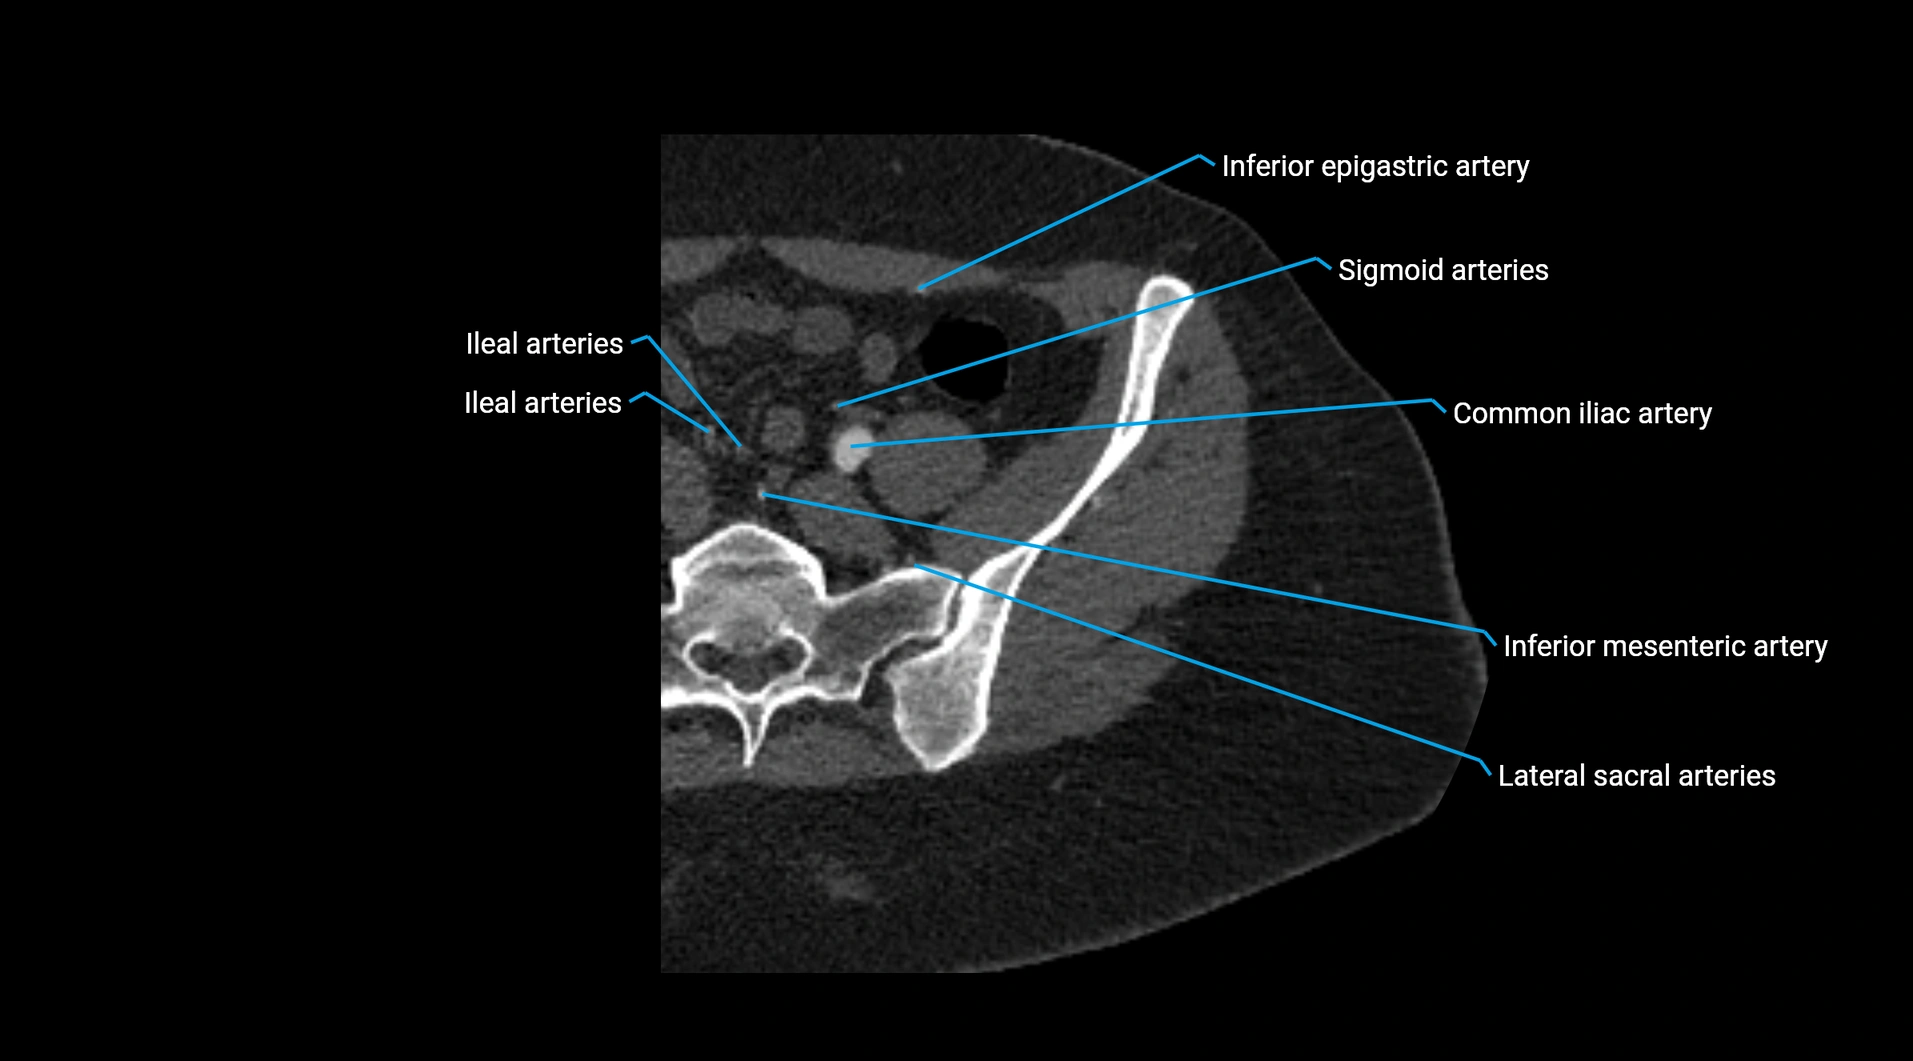

CT images

image

Contrast-enhanced CT (CTA):

• Gold standard for abdominal aortic imaging

• Provides excellent detail of lumen, wall, aneurysm, thrombus, and branch vessels

• Multiplanar and 3D reconstructions help in aneurysm measurement, stent graft planning, and dissection evaluation

• Unpaired visceral branches: celiac trunk, superior mesenteric artery (SMA), inferior mesenteric artery (IMA)

• Paired visceral branches: middle suprarenal arteries, renal arteries, gonadal arteries (testicular or ovarian)

• Parietal branches: inferior phrenic arteries, lumbar arteries, median sacral artery

• Terminal branches: right and left common iliac arteries